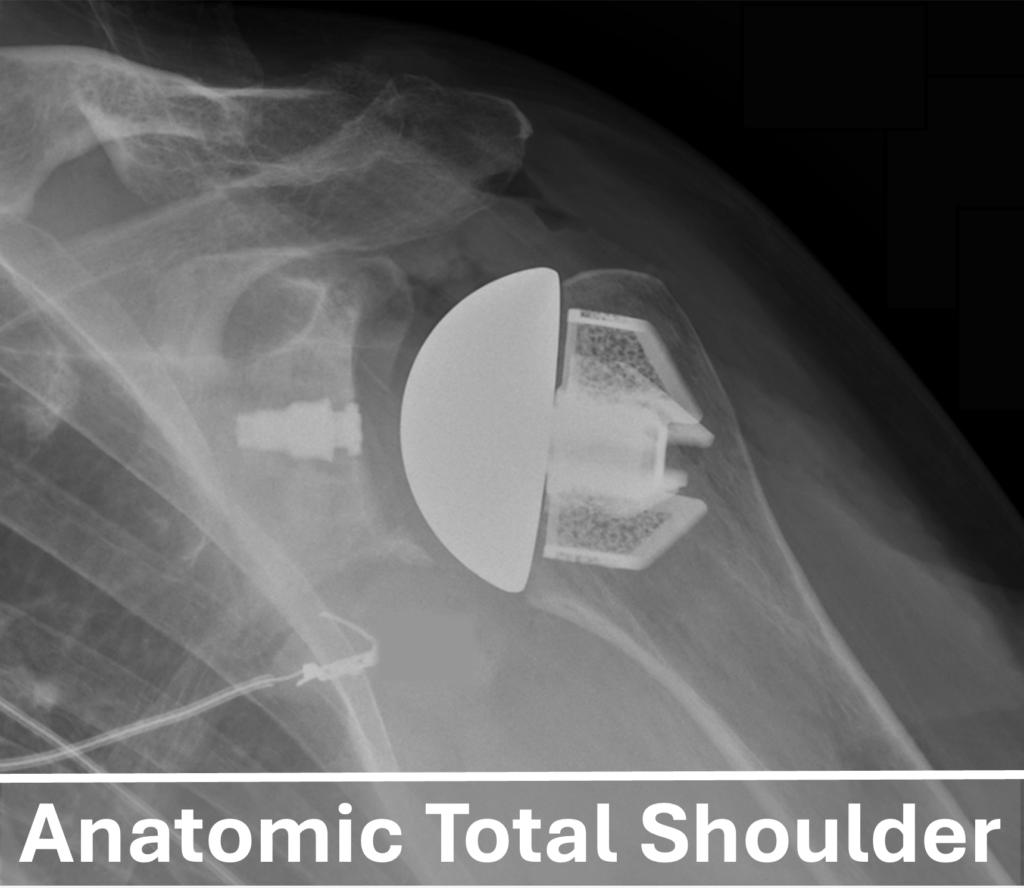

An Anatomic Total Shoulder Arthroplasty (TSA) involves resurfacing the arthritic ball-and-socket shoulder joint. In this procedure, the damaged humeral head (ball) is replaced with a metal component, while the glenoid (socket) is replaced with a high-strength plastic component. This combination allows for the restoration of the shoulder’s natural ball-and-socket structure thereby reducing pain and improving shoulder function.

stemless Anatomic Total Shoulder Arthroplasty is a modern variation of this procedure. In this approach, the humeral head (Ball) is replaced with a bone-preserving “stemless” metal porous coated component that sits near the cut surface of the humerus, eliminating the need to remove more of the native bone. The advantages of a stemless total shoulder arthroplasty include less bone removal, a quicker operation, and reduced initial postoperative pain. Due to these positive outcomes, Dr. Marigi predominantly utilizes the stemless anatomic total shoulder technique in his replacements and has published articles highlighting its benefits.